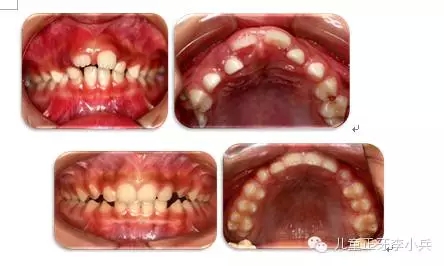

3. 牙槽骨早期塑形矯治:良好的咬合必須是上下頜骨大小位置正常、上下牙大小排列正常,以及上下牙弓的大小與形態(tài)協(xié)調(diào)。臨床功能矯形可調(diào)整上下頜骨大小與位置的不調(diào);臨床正畸治療可矯治牙齒排列異常。而上下牙槽骨的大小形態(tài)不協(xié)調(diào)的早期矯治就是牙槽骨的早期塑形。牙槽骨的發(fā)育包含牙槽骨長(zhǎng)、寬、高三項(xiàng)的發(fā)育,常見(jiàn)的牙槽骨發(fā)育異常是寬度的不足,形成功能性下頜后縮及牙列擁擠。早期的牙槽骨括弓能打開(kāi)腭中縫,擴(kuò)大牙弓寬度,增加牙弓周徑,避免功能性II類及擁擠的發(fā)生。(圖4,早期牙槽骨塑形矯治)

圖4 上頜牙弓狹窄,牙槽骨擴(kuò)弓塑形促進(jìn)上下牙弓正常發(fā)育;